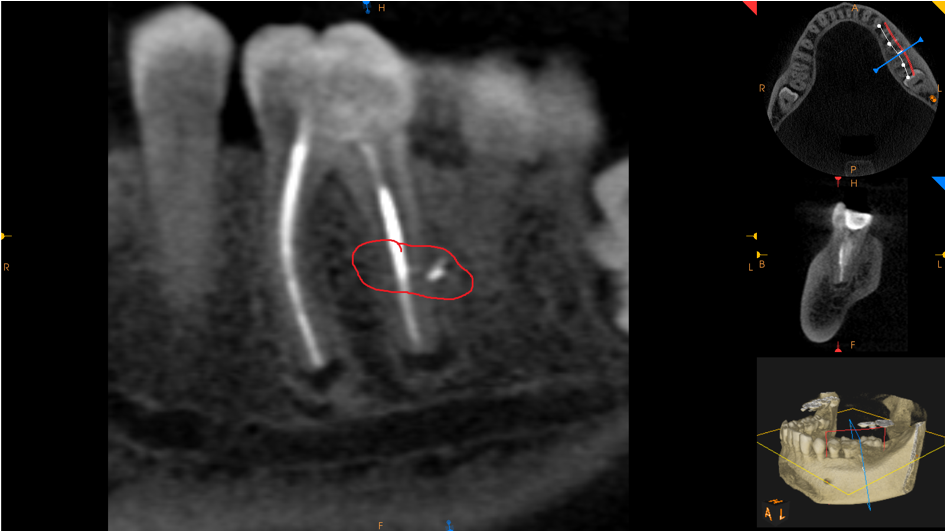

Ząb 36 – po leczeniu kanałowym. Wypełnione trzy kanały. Kanały dystalny i policzkowy wypełnione na całej swojej długości, w kanale językowym w części przywierzchołkowej materiał wypełniający niewidoczny (2mm). Wokół wierzchołków korzeni widoczne ogniska rozrzedzenia struktury kostnej o średnicy: korzeń mezialny – 2mm x 3mm, dystalny 3,5mm x 3mm.

Obecność uszczelniacza endodontycznego z boku korzenia oraz radiologiczne przejaśnienie widoczne w tym miejscu w tkankach korzenia dystalnego mogą sugerować uszkodzenie korzenia w tym obszarze.